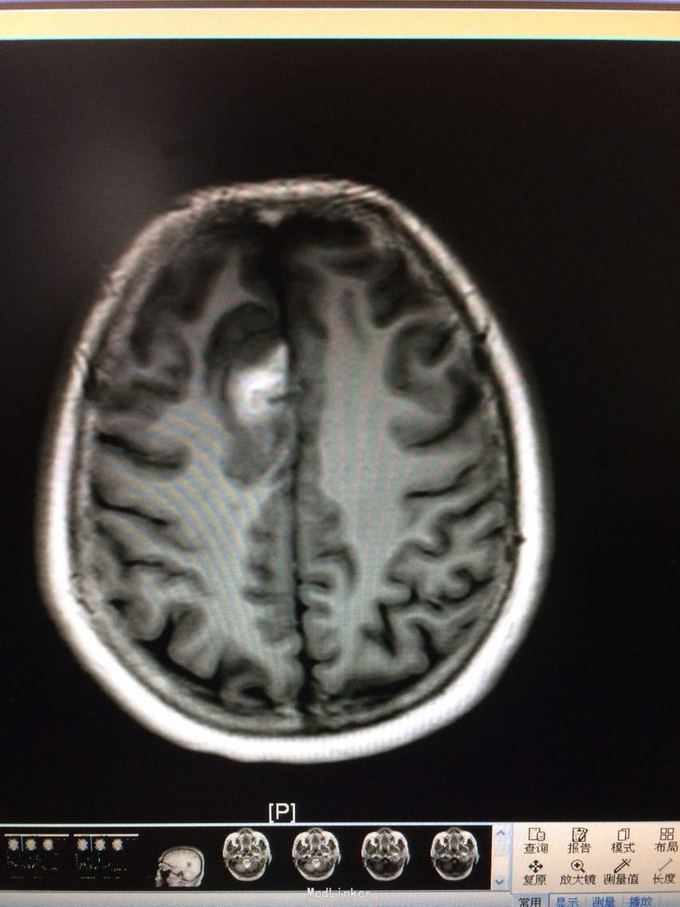

主诉:记忆力减退3月,左侧肢体乏力3天 病史:患者51岁女性,3月前无明显诱因出现记忆力减退,伴头痛,3天前出现站立不稳,左侧肢体乏力,步行困难,当地CT提示右侧额叶低密度灶,

查体:左侧上肢肌力4级,右侧5级,轻瘫试验左侧阳性 辅助检查:右侧额叶、胼胝体膝部病变伴出血,增强扫描明显强化。考虑胶质瘤

诊断:右侧额叶多发脑软化灶 处理:全麻下行右侧额叶占位病变切除术,术后病理提示:符合脑软化,未见明显肿瘤因素等